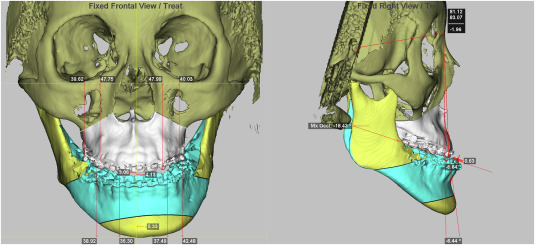

برنامه ریزی جراحی فک فرایندی بسیار دقیق و چند مرحله ای است که باید با همکاری نزدیک جراح فک و صورت، ارتودنتیست و گاهی متخصص خواب، گفتار درمانگر و جراح پلاستیک صورت انجام شود. تصویربرداری سه بعدی قلب این برنامه ریزی است. پس از تهیه سی بی سی تی، تصاویر به نرم افزار های تخصصی منتقل می شود و در آنجا جراح می تواند مدل سه بعدی فک ها را مشاهده، برش های مجازی ایجاد و حرکت های مختلف استخوان را شبیه سازی کند. این شبیه سازی شامل جابه جایی فک بالا و پایین در سه محور، چرخش ها، اصلاح عدم تقارن ها و حتی بررسی تاثیر این جابه جایی ها بر روی پروفایل صورت و لبخند است. به کمک این نرم افزار ها، جراح می تواند قبل از ورود به اتاق عمل، نسخه ای بسیار نزدیک به واقعیت از نتیجه را ببیند.

این نوع برنامه ریزی دیجیتال نه تنها دقت را بالا می برد، بلکه زمان جراحی را کوتاه تر و ریسک خطا را کاهش می دهد. علاوه بر این، از روی داده های سه بعدی می توان گاید های جراحی یا اسپلینت های راهنما چاپ سه بعدی کرد که در اتاق عمل مانند یک قالب دقیق روی دندان ها و فک بیمار قرار می گیرد و به جراح نشان می دهد فک ها دقیقا باید در چه موقعیتی فیکس شوند. این روش نسبت به روش های سنتی که بر اساس اندازه گیری های دستی و مدل های گچی بود، خطای بسیار کمتری دارد. همچنین امکان ذخیره سازی فایل ها و مقایسه قبل و بعد از جراحی وجود دارد که برای ارزیابی نتیجه، آموزش و حتی امور قانونی ارزشمند است. در نهایت، برنامه ریزی سه بعدی به جراح اجازه می دهد به صورت فرد محور و اختصاصی برای هر بیمار طرح درمان ویژه طراحی کند.

جراحی ارتوگناتیک یا جراحی اصلاح ناهنجاری های فک، یکی از پیچیده ترین جراحی ها در حوزه فک و صورت است که هدف آن اصلاح رابطه فک بالا و پایین، بهبود عملکرد جویدن و صحبت کردن و همچنین بهبود زیبایی چهره است. در این جراحی معمولا نیاز است بخش هایی از استخوان فک برش داده و در موقعیت جدید فیکس شود. کوچک ترین اشتباه در محاسبه زاویه و میزان جابه جایی می تواند باعث ایجاد مشکلات جدید در bite، درد مفصل، عدم تقارن یا نارضایتی ظاهری شود. به همین دلیل تصویربرداری سه بعدی به عنوان استاندارد جدید در برنامه ریزی جراحی ارتوگناتیک شناخته می شود. مطالعات جدید نشان داده اند استفاده از سی بی سی تی و برنامه ریزی دیجیتال سه بعدی، دقت پیش بینی نتایج جراحی و تطابق طرح قبل از عمل با نتیجه واقعی را به طور قابل توجهی افزایش می دهد.

در عمل، ابتدا سی بی سی تی و اسکن داخل دهانی از بیمار گرفته می شود و سپس هر دو در نرم افزار ادغام می شوند تا مدل سه بعدی دقیق دندان ها و فک ساخته شود. سپس جراح و ارتودنتیست روی این مدل، جابه جایی های لازم را شبیه سازی می کنند و بر اساس آن، اسپلینت های جراحی چاپ سه بعدی می سازند. حتی در برخی مراکز پیشرفته از گاید های برش اختصاصی استفاده می شود که روی استخوان می نشینند و محل دقیق برش ها را نشان می دهند. در نهایت، با استفاده از این ابزار ها، نتیجه جراحی به طرح دیجیتال بسیار نزدیک می شود. برای بیمار نیز دیدن شبیه سازی سه بعدی قبل از عمل، باعث درک بهتر از فرایند، کاهش استرس و تصمیم گیری آگاهانه تر می شود. این روند کاملا در راستای استاندارد های روز دنیا برای مراقبت های پزشکی با کیفیت بالاتر و فرد محور است.